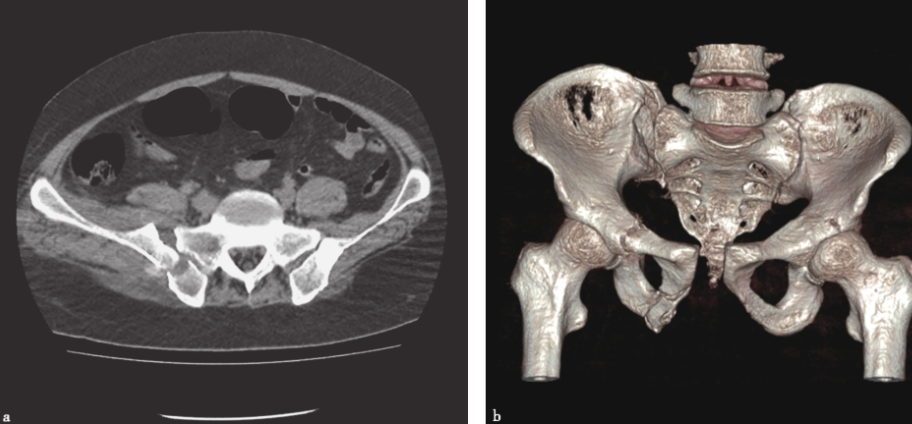

使用CT检查可以充分显示骨盆后方与韧带的结构。尤其是当骶骨骨折伴有大量肠气和粪便时,骨盆X线片容易造成漏诊,这时CT检查就非常有帮助。CT三维及多平面重建可获得任意平面的图像及任意旋转的三维立体图像,为临床医师整体、全面观察骨盆骨折提供了直观立体的图像,为骨折类型的诊断及手术设计提供了极大的帮助。骨盆受到外力损伤后骨性三维成像可清晰、完整地显示整个骨盆损伤后的形态变化及骨折情况,特别是对有移位的断端,在三维重建模式下可全面地了解断端上下、左右、前后的移位及程度,对于X线片不能发现疑似的隐匿性骨折,也可以在多平面重建成像中得以证实或排除。因此,三维成像的结果对实施手术的方式和骨折的固定有很重要的指导作用,并可依此对患者进行预后评估。对于确定骨盆背侧损伤的机制,CT检查时可以发现通过骶骨的损伤是压缩伤还是剪切力损伤。骶髂关节移位程度对于确定背侧损伤的稳定性是很有价值的。若关节张开的程度继续加大,后方韧带将断裂,损伤将变为不稳定型(C型)。CT还有助于了解有无髋臼骨折。很多接近前柱的耻骨支骨折容易合并髋臼骨折,近年来发展起来的三维CT对骨盆骨折的诊断帮助更大。Obaid报道了174例骨盆骨折病例,其中51%被X线片漏诊,最后由CT确诊,这些骨折大多发生在骶髂区域(图13)。

图13骨盆骨折CT表现显示双侧骶骨骨折;三维重建显示右骶髂关节间隙增宽,耻骨联合分离,右髋臼横行骨折